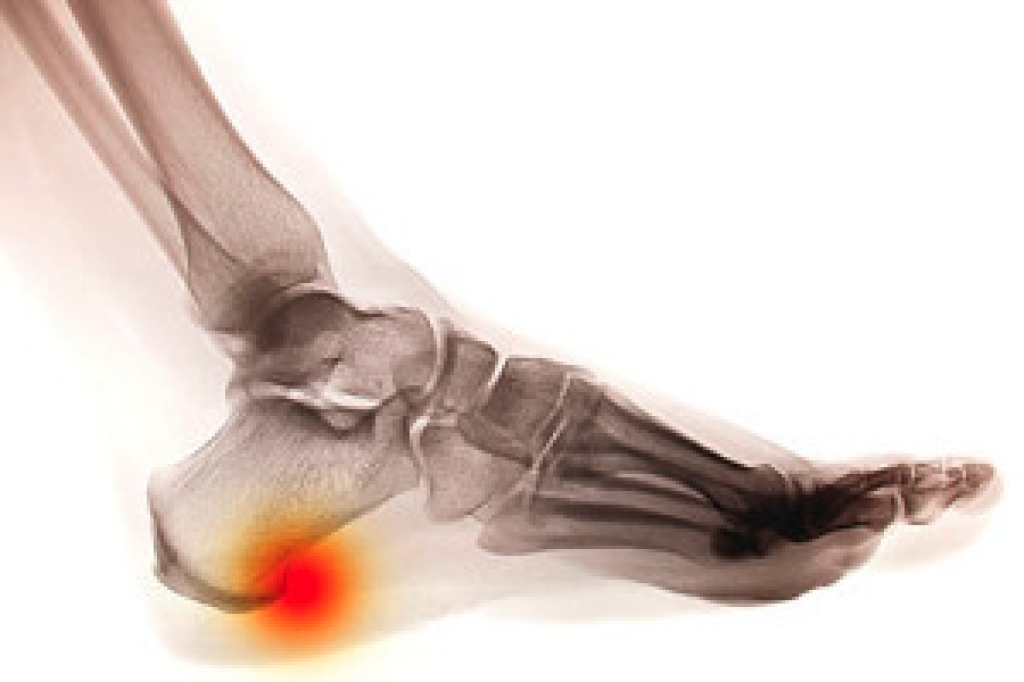

Numbness in the feet can range from temporary and harmless to a sign of a more serious condition. Numb feet often result from pressure on nerves, such as sitting with the legs crossed or wearing shoes that lack adequate support, which can temporarily disrupt nerve signals. More persistent numbness may be linked to peripheral neuropathy, a condition that develops when nerves in the feet are damaged, leading to tingling, burning, or loss of feeling. Reduced blood flow is another common cause of numb feet, as conditions like peripheral artery disease may limit oxygen supply to the nerves and tissues of the feet. In some cases, spinal problems, such as a herniated disc, can also interfere with nerve pathways to the feet, causing sensory changes. A podiatrist can evaluate the cause of foot numbness, provide treatment to protect foot health, and help prevent complications. If you are experiencing frequent foot numbness, it is suggested that you schedule an appointment with a podiatrist for an exam and appropriate treatment.

Neuropathy is a condition that leads to damage to the nerves in the body. Peripheral neuropathy, or neuropathy that affects your peripheral nervous system, usually occurs in the feet. Neuropathy can be triggered by a number of different causes. Such causes include diabetes, infections, cancers, disorders, and toxic substances.